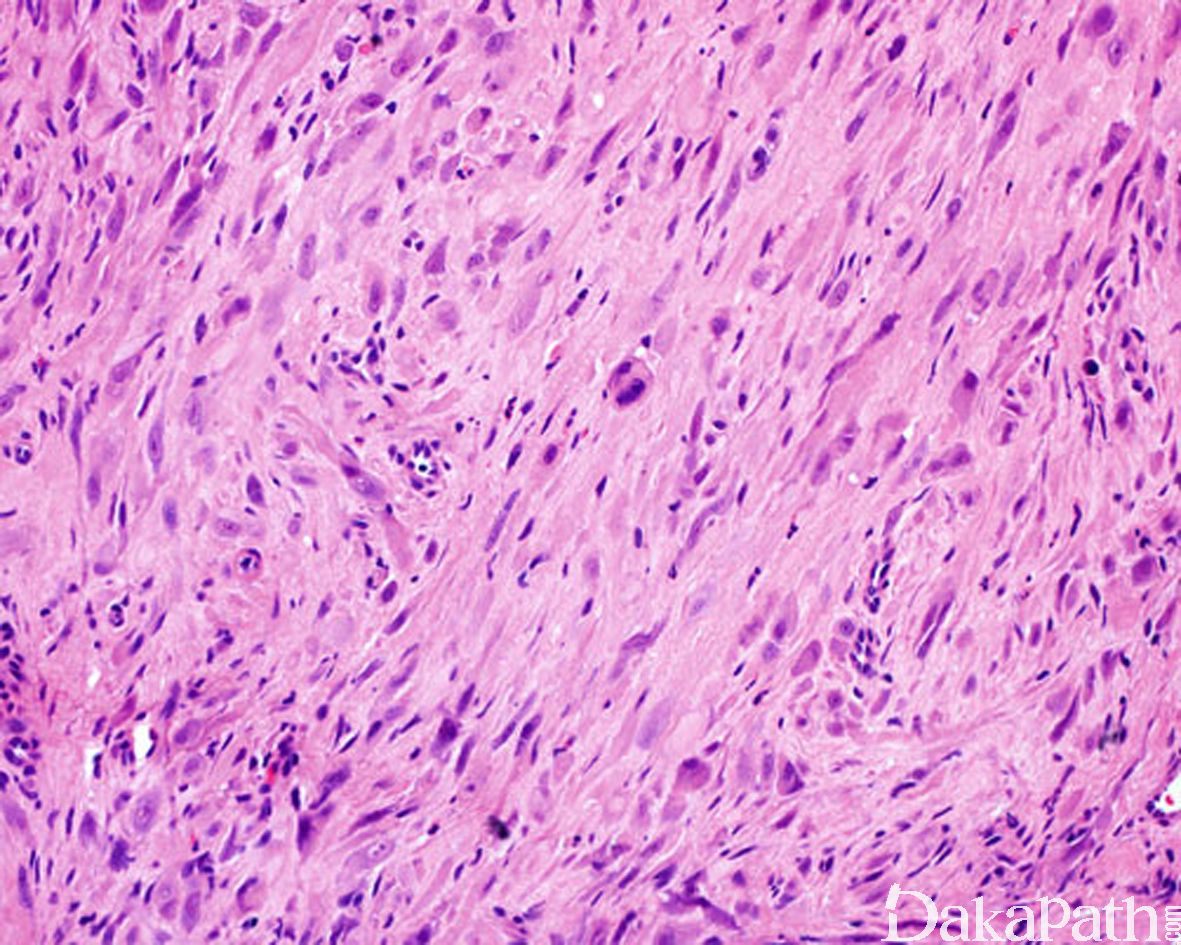

4. 瘤细胞胖梭形,部分呈上皮样,具丰富的嗜酸性胞质;

5. 上皮样细胞可呈上皮样肉瘤样细胞或横纹肌母细胞样;

7. 瘤细胞多形性不明显,核空泡状,具小核仁,核分裂像少见,通常少于 2/10HPF;

8. 少数病例可显示明显核异型、核分裂增多;